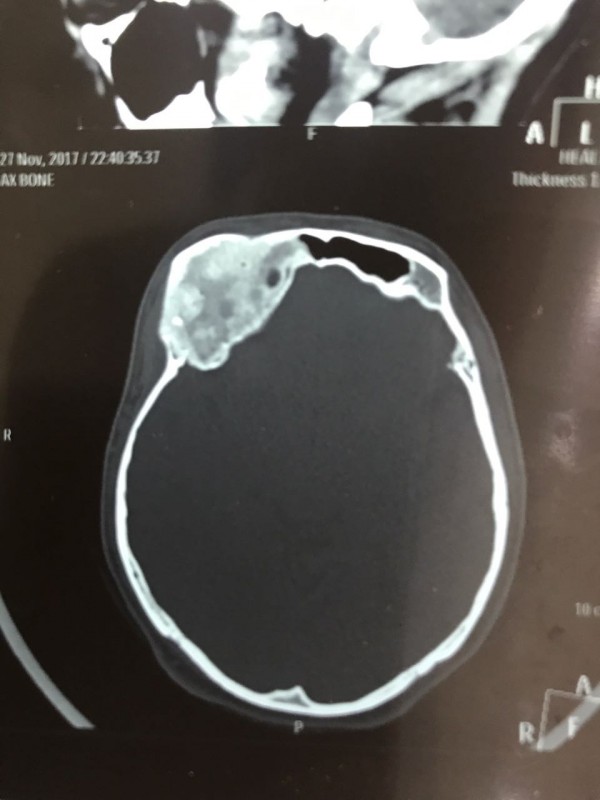

Как рассказал врач-нейрохирург городской клинической больницы № 7 Алматы Константин Ли, предварительный диагноз пациента - "фиброзная дисплазия лобной кости справа", то есть опухолевое поражение костей черепа. По его словам, сложность и уникальность операции в том, что опухоль плотно соприкасалась со зрительным нервом.

"Компьютерная томография показала, что костная опухоль поражала лобную кость и "крышу" орбиты глаза, которая, в свою очередь, сдавливала глазное яблоко. Чтобы убрать опухоль, потребовалось немало времени. Наша задача была сохранить глазное яблоко, зрительный нерв и сосуды. Если неправильно провести операцию и неправильно закрыть дефект, то в последующем это может привести к эстетической неполноте и асимметрии лица. Уникальность еще и в том, что в операции применялась 3D-стереолитография, которая делается только в Алматы", - рассказал он.

Снимок сделан до операции. Фото предоставлено Константином Ли